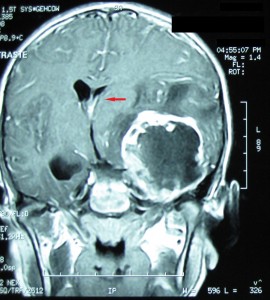

En la actualidad el diagnóstico de los tumores cerebrales mediante el empleo de las novedosas técnicas de imagenología suele ser bastante preciso. De esta manera, la implementación de un tratamiento eficaz comprende la combinación de tres herramientas esenciales: la cirugía, la radioterapia y la quimioterapia. Aunque por supuesto la elección del tratamiento más oportuno dependerá siempre del tamaño, tipo, localización y velocidad de crecimiento del tumor, así como del estado general de salud del paciente.